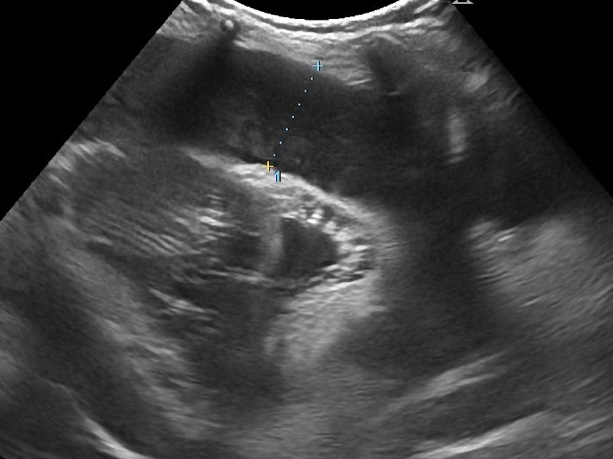

すぐに超音波検査を行ったところ、心臓の周囲に多量の液体(心嚢水)がたまっている状態(心嚢水貯留)が確認されました。

手術前の心臓のエコー画像・レントゲン画像・貯留した心嚢水により心臓が圧排されている。